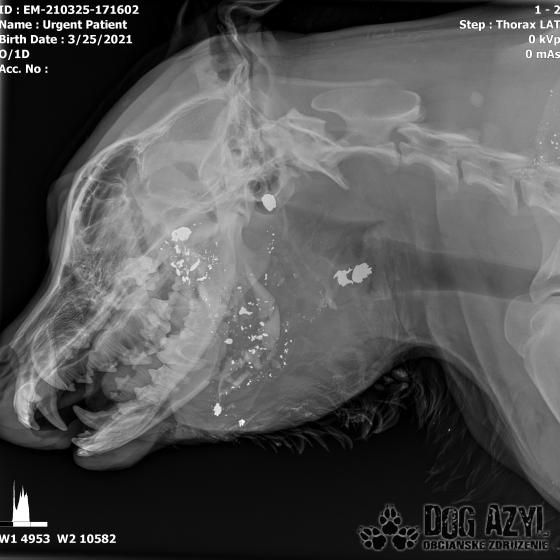

Strela zasiahla Barisa v oblasti lícnej kosti, ktorá mu rozdrvila sánku a následne putovala cez krk až po krčnú chrbticu. Úlomky z guľky (neviem ako sa to odborne volá) sa roztrieštili na "milión" kusov počas svojej cesty. Tieto úlomky sú všade (ako vidieť aj na RTG). Jeden (alebo niekoľko týchto úlomkov) sa dostali až po miechu, ale našťastie ju neprerazili. Toto spôsobilo, že Baris citlivosť v nohách na ľavej strane sice má, ale má poškodenú motoriku. Tieto úlomky sa z oblasti stavcov, miechy aj krku dnes odstránili, ale Barisko z ďaleka nemá vyhraté. Miecha je totiž zakrvácaná (opäť sa ospravedlňujem za nepresnosť a laickosť) a to, že ako veľmi je poškodená, alebo či jeho slabosť bola spôsobená "iba opuchom" sa ukáže cca do 24 hodín. Ak Baris nedajbože do zajtra stratí citlivosť v nohách, tak.. žiaľ... Ale! ak citlivosť zostane, prípadne nastane aj zlepšenie, tak vzplanie plamienok ďalšej nádeje a bojujeme ďalej!